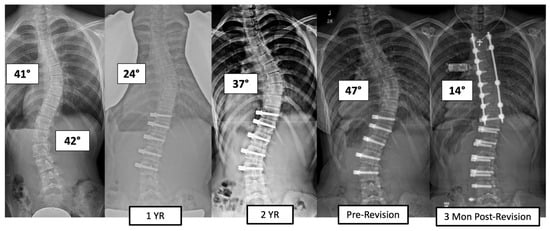

There were four major complications (10.8%), including one readmission and three patients who required re-operation. Patient 1 underwent re-operation due to radiculopathy caused by a screw tip impinging on a nerve root in a lumbar foramen requiring screw revision and replacement of the tether. At 3 years post operation, they have a broken tether at one level, but no further revision is needed. Patient 2 had progression of a previously uninstrumented thoracic minor curve which progressed following lumbar tether breakage. This was revised with fusion of the previously untreated thoracic curvature and the addition of a second row of screws and second tether for the thoracolumbar construct (Figure 3). Patient 3 had overcorrection of the thoracolumbar curvature and adding on of the thoracic. As a result, the tether was released in the thoracic region and the thoracolumbar tether was revised (Figure 4). One patient (3%) required readmission due to an inability to tolerate post-operative pain medication. During admission, pain was controlled, and they were discharged without sequela.

Figure 3.

This is a 13-year-old female who experienced progression of the thoracic curve following tether breakage in the lumbar spine. The patient was revised with fusion of the previously untreated thoracic curvature and addition of a second row of screws and second tether for the thoracolumbar construct.

Figure 4.

This is an 11-year-old female who experienced overcorrection of the thoracolumbar curvature and adding on of the thoracic. A revision operation was performed to release the tether in the thoracic region and revise the thoracolumbar tether.